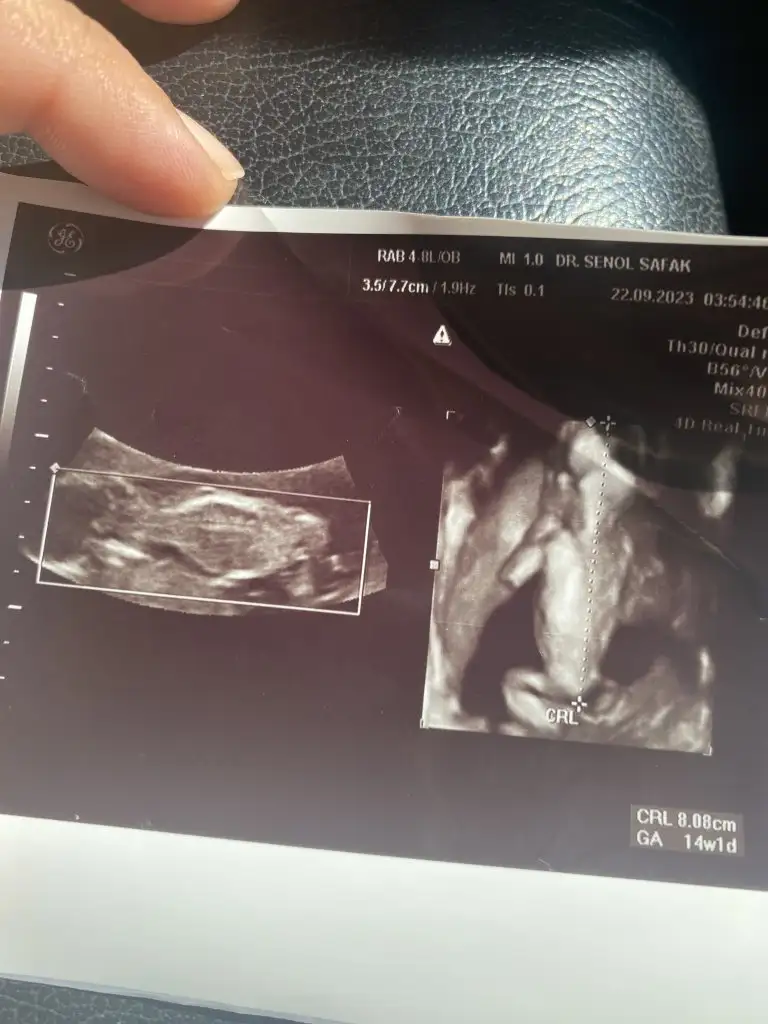

Sırtı dönük üç boyutlu tipe bakın ya😂küçük kurbağam🫶bu arada 16.haftadan önce cinsiyet açıklamayı sevmem ama erkek hani dedi yüksek ihtimalle eşim tekrar sorunca erkek gibi dedi💙

• IMG_4821.webp

IMG_4821.webp

37,7 KB · Görüntüleme: 70